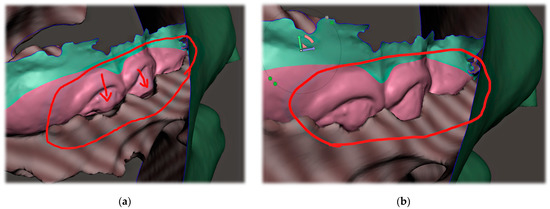

Only the parts in contact with the appliance were relevant from the CT and were exported in STL format and later aligned with the STL output from the intraoral scanning, as is shown in Figure 5a,b.

The correct alignment of the intraoral scan with the CT is very important, as the accurate intraoral scan provides detailed information about the location where the appliance will be placed. Misalignment might lead to an extremely different orientation of the spur from what was intended. This can lead to the patient choking, extreme gag reflex or damage to the mucous membrane of the pharynx. The alignment of the segmented CT and intraoral scan can be performed in various programs, including Meshmixer™ (Autodesk®, Inc., San Rafael, CA, USA), as is shown in Figure 6.